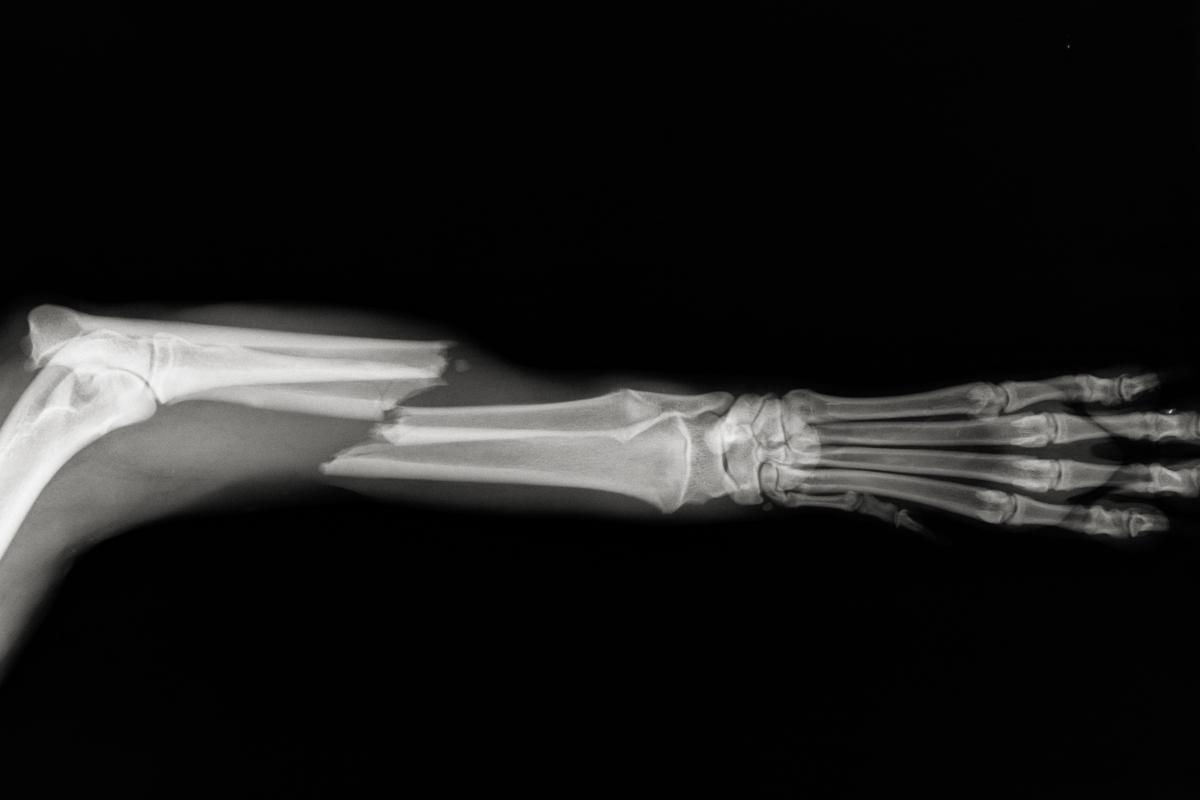

Fraturas

Outro problema que causa grande dor nos cachorros e que pode ser a razão pela qual seu cachorro grita de dor do nada são as fraturas. Elas consistem na quebra de um ou mais ossos do animal devido a uma grande força exercida sobre eles. Elas podem ocorrer devido a brigas entre cachorros, quedas, acidentes ou qualquer trauma que aplique força suficiente para fraturar o osso. Geralmente, os cachorros afetados por fraturas gritam quando você tenta pegá-los ou tocar na área fraturada.

Os cachorros podem fraturar muitos dos ossos que compõem seu esqueleto, isto é, não apenas os das patas, mas também a pelve, as costelas ou a mandíbula. A dor é o primeiro sintoma associado às fraturas e é rapidamente acompanhada por um processo inflamatório. No caso de fraturas na mandíbula, o cachorro pode apresentar perda de apetite; no caso de fraturas na pelve, podem manifestar claudicação ou paralisia na parte posterior; e, por fim, no caso de fraturas nas costelas, podem apresentar dificuldade respiratória. Recomendamos a leitura destes artigos: